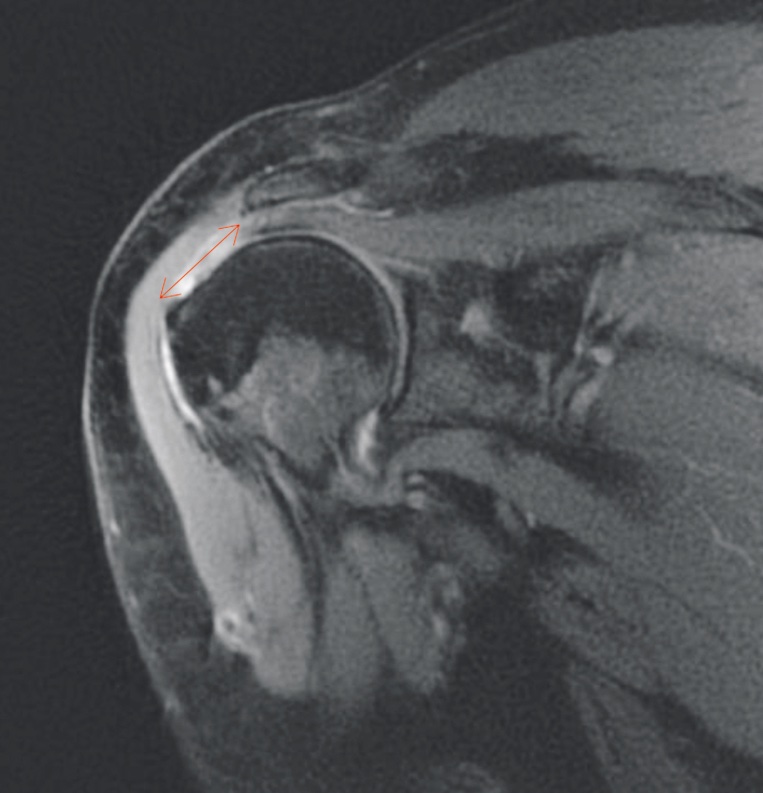

La risonanza magnetica è una tecnica più costosa, non invasiva, che consente di ottenere immagini ad alta risoluzione su più piani, sebbene statiche (Fig. 1).

La RMN mostra risultati simili a quelli dell’ecografia nel riconoscimento delle lesioni di cuffia a tutto spessore (94% di sensibilità e 93% di specificità), ma nei pazienti con lesioni parziali la sensibilità della risonanza magnetica è molto più alta di quella dell’ecografia (74% e 52%, rispettivamente) 4. Inoltre, la RMN è in grado di rilevare l’infiltrazione adiposa e l’atrofia dei muscoli della CDR. L’utilizzo del mezzo di contrasto (artro-RMN) non sembra migliorare l’accuratezza diagnostica della RMN ed è associata a maggiore invasività e discomfort per il paziente.